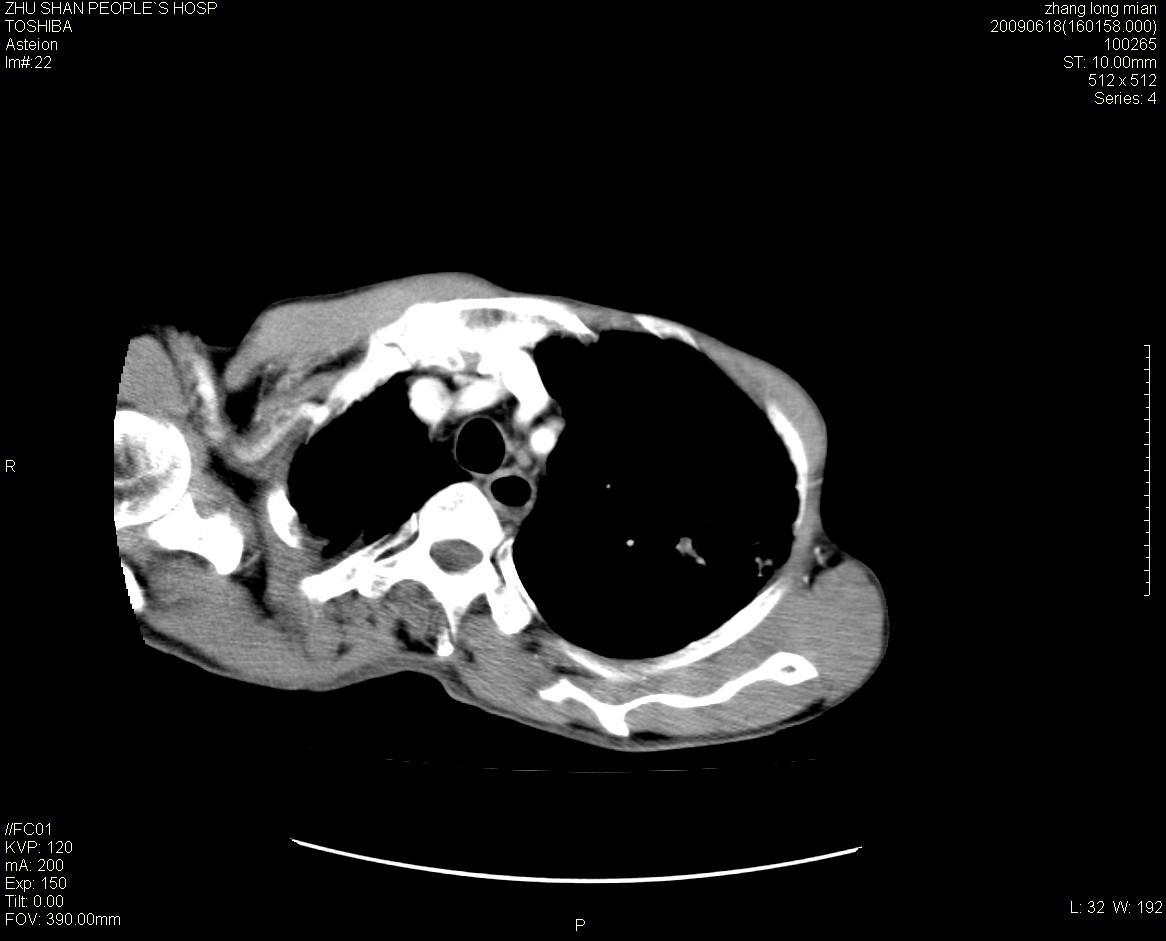

男性 65岁 胸片发现右下肺包块.诊断肺ca并纵隔转移没有问题吧!

两侧胸廓不对称,右侧呈塌陷改变,右肺萎缩。

右下肺见浅分叶状软组织块影,边缘有毛刺,其下部似见不完整偏心空洞影,邻近胸膜凹陷征,并胸腔积液。

增强见纵隔区气管隆突上下及左肺门区肿大淋巴结。左肺感染性病灶。

另见右上肺见一枚小结节影,性质待定。